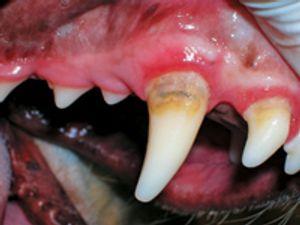

Patients with periodontal disease, the most common disease in dogs, suffer from progressive inflammation and destruction of the tissues supporting the teeth.

Chronic ulcerative paradental stomatitis (CUPS) is a painful condition in dogs that is also known as ulcerative stomatitis, idiopathic stomatitis, and lymphocytic-plasmacytic stomatitis.